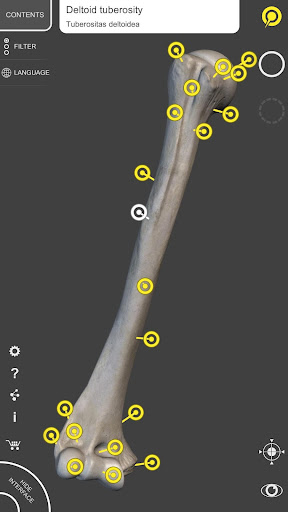

"Skeleton | 3D Atlas of Anatomy" is a next generation anatomy atlas in 3D which gives you availability of interactive highly detailed anatomical models!

Each bone of the human skeleton has been reconstructed in 3D, you can rotate and zoom in on each model and observe it in detail from any angle.

By selecting models or pins you will be shown the terms related to any specific anatomical part, you can select from 12 languages and show the terms in two languages simultaneously.

• Surfaces of the skeleton with high resolution textures up to 4K

• Rotate and Zoom every model in the 3D space

• Interactive Pin allow visualization of the term relative to every anatomical detail